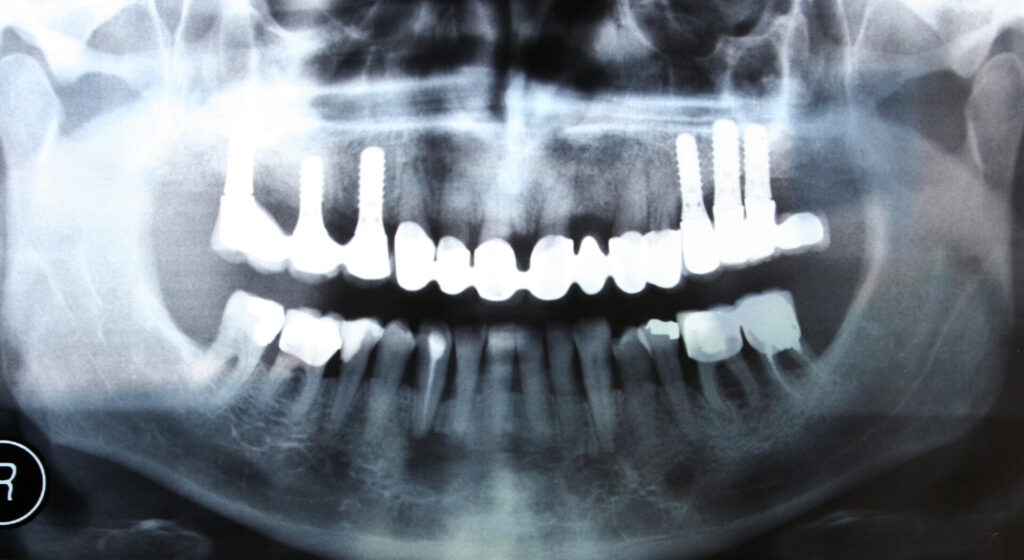

歯科用CTを使用して、顎骨の形状や骨密度を立体的に把握します。

これにより、インプラントを埋入するための適切な位置や角度を、より正確に測ることができます。